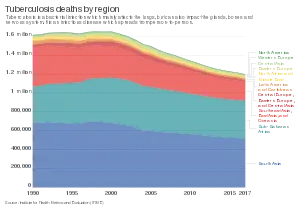

| Chest X-ray of a person with advanced tuberculosis: Infection in both lungs is marked by white arrow-heads, and the formation of a cavity is marked by black arrows. | |